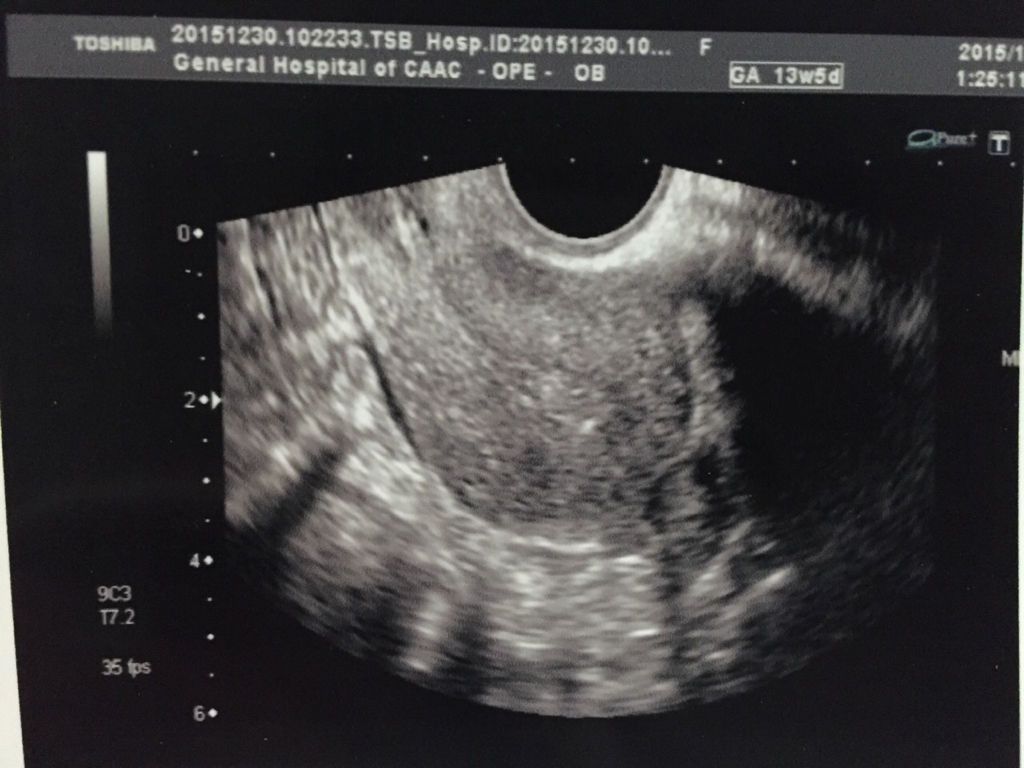

想要宝宝做了孕前检查,其中阴超报告医生说排卵少,有点多囊卵巢什么的,什么意思呢?严重吗?影响要宝宝 想要宝宝做了孕前检查,其中阴超报告医生说排卵少,有点多囊卵巢什么的,什么意思呢?严重吗?影响要宝宝吗?请高手医生给看看。谢谢。本人27周岁。 点击展开 匿名用户 2015-12-31 22:52 满意回答 从超声检查来看卵泡不够寸串圆润,是否能够成概兔吉熟排出还告搂需要后期监测才可以。没看到多囊提示。 东郭灵慧_eGp2 2015-12-31 23:00 宝宝知道提示您:回答为网友贡献,仅供参考。 为您推荐: 其他回答 就是卵子不大好 匿名用户 2015-12-31 22:56 相关问题 在丰城妇产医院孕前检查出多囊卵巢了,这个对身体有什么不好影响吗?会不会影响排卵? 我是多囊卵巢综合症,7月10号来的月经,25测的排卵同房,30号小腹疼痛了一天,请问这是怎么回事? 我是多囊卵巢综合证,孕前吃过二